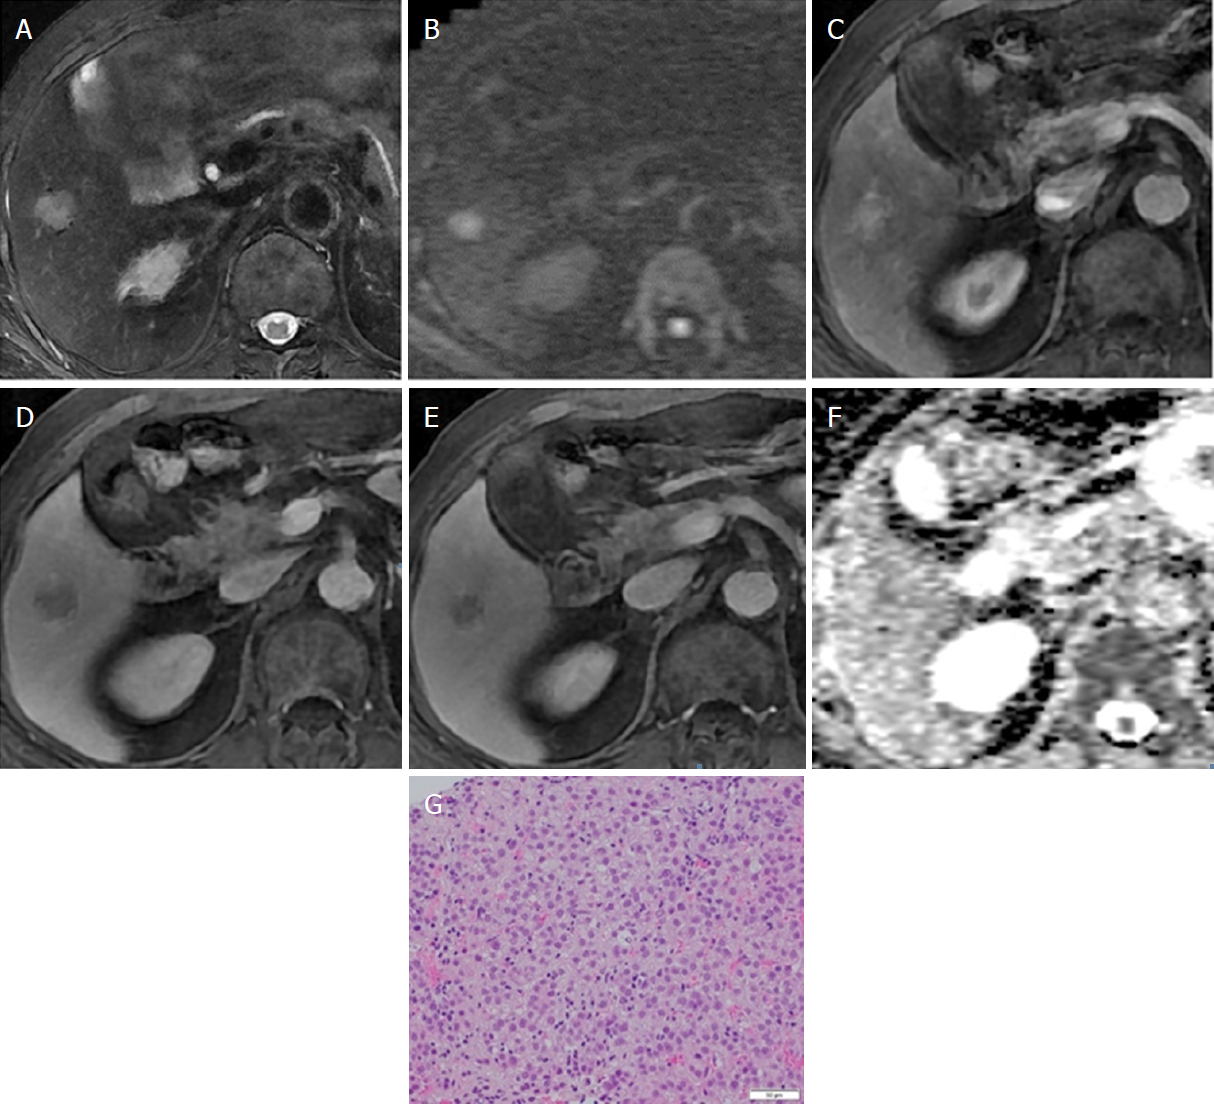

A 22yearold man with fibrolamellar HCC. Notes (A) Axial Hcc Eovist Radiology eovist ® (gadoxetate disodium) injection is indicated for intravenous use in magnetic resonance imaging (mri) of the liver to detect and characterize. the unique imaging characteristics of hcc lesions, deriving mainly from the assessment of their. hepatocellular carcinomas (hccs) usually show hyperenhancement in the arterial phase, with washout in the. hepatocellular carcinoma (hcc), also called hepatoma,. Hcc Eovist Radiology.